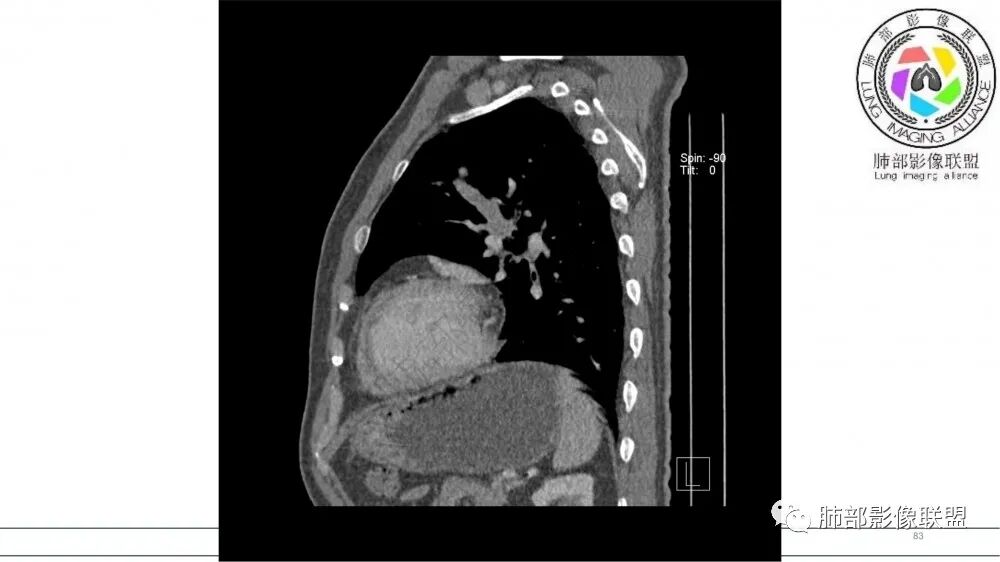

左肺上叶前段支气管内铸形生长软组织影,增强后均匀强化,远侧见斑片状磨玻璃影。考虑恶性病变,粘表?粘液腺?

老年男性,左肺上叶前段支气管内铸形阴影,增强后病灶不均匀强化,内部有坏死?远端可见斑片状阴影(阻塞性肺炎)。考虑恶性病变,老年人,鳞?类癌?粘表不能排除。

老年男性,吸烟史,左肺上叶支气管塑形生长肿块,整体边缘较圆钝,不均匀强化,血管走形,形态较纤细,病灶远端可见花草样改变,恶性,先考虑小细胞癌鉴别鳞癌

左肺上叶尖后段支气管近端截断,远端见高密度铸型,远侧见阻塞性改变,老年男性,吸烟史,考虑恶性,鳞癌。ABPA代排

老年男性,长期吸烟史。左上肺前段沿支气管走形的指套样病变,增强可见病灶强化(排除结核、ABPA(也无气喘症状)),远端多发点状高密度影。考虑恶性肿瘤,鳞癌可能性大。

老年男性,术前检查肺气肿背景,左肺上叶结节,沿支气管蠕虫样生长,左肺门及纵隔淋巴结肿大,增强扫描不均匀强化,血管包绕,结合吸烟史,考虑小细胞肺癌。

老年吸烟男性,尖前段支气管内塑形生长,增粗蠕虫样,没有肺不张(排除鳞癌?),远端少许阻塞肺炎,增强低强化,锁定小

老年男性,吸烟,指套征,蠕虫征,阻塞性炎症不严重。可见血管穿行,密度均匀,轻度强化,首先考虑小细胞肺癌。鉴别鳞

2021年8月6日晨读病例结果:小细胞肺癌

指套征:是影像征象,胸部平片表现为手指状密度增高影,以肺门为中心呈放射状分布,CT显示扩张支气管内低密度黏液栓形成或实性病变,呈管状、树枝状或卵圆形密度增高影;支气管扩张伴近端梗阻时,扩张支气管内部黏液分泌物不能排出而形成。可以伴随远端空气潴留征、阻塞性炎症。

研究报道,中心型 SCLC 经 CT 扫描后通常支气管表现为鼠尾样狭窄,肺门或纵隔肿块明显,由于肿块沿管壁生长表现为顺延支气管形态的不规则形状。病灶相对特征性影像学表现比如鸭蹼状、腊肠状、葫芦状及葡萄状改变,可以出现血管包埋,很少有空洞、空泡,较少引发肺不张,阻塞性炎症成都较轻。与一般肺癌比较,恶性程度高,侵袭力强、病灶很小就容易远处转移!Herzberg 等[19]研究指出,20%以上 SCLC 倍增时间短,预后不良。